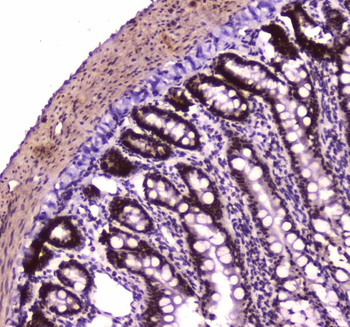

Immunohistochemistry of paraffin-embedded human colon using orb631314 (SMARCA4 Antibody) at dilution of 1:50.